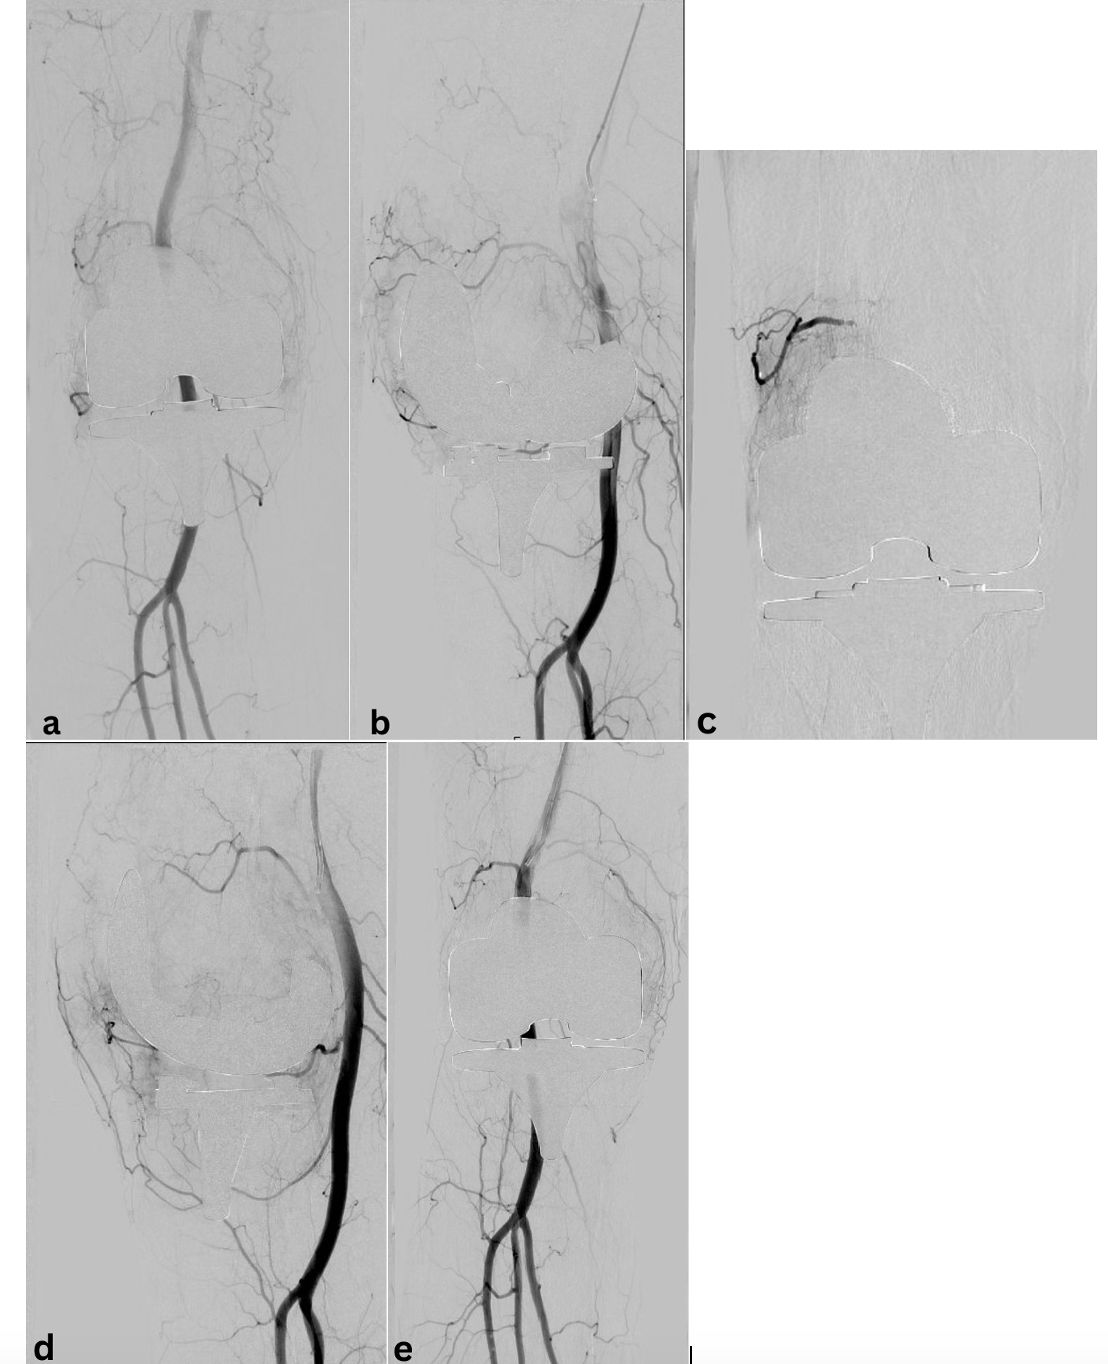

Oblique imaging may be necessary to identify the origin of the genicular arteries, particularly in the postoperative setting. Angiography will aid in identifying areas of synovial blush with the joint space. This finding is largely thought to be representative of synovial hyperemia secondary to angiogenesis. The 5F base catheter should be advanced as close as possible to the ostium of the desired genicular branch for stability as the microcatheter system is deployed. Standard microcatheter systems (2.4F to 2.8F) may not be successful for smaller tortuous vessels, and a smaller system may need to be utilized. For hemarthrosis, embolization is performed using particles ranging from 300 to 500 µm.13 In the setting of GAE treatment for OA, studies have been performed using much smaller particles, typically ranging from 100 to 300 µm. Larger embolic particles may be associated with reduced nontargeted embolization, such as cutaneous branches and those supplying ligamentous components of the joint.14 The endpoint of embolization is pruning of the neovascularity with preservation of the normal genicular artery.

See Figure 1 and Figure 2 for cases of knee OA treated with GAE.